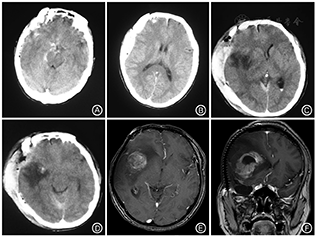

患者男,45岁,2009年4月在工地上从3~4 m高度坠落造成脑外伤。当时昏迷并在外院行头颅CT检查发现右侧额颞叶硬膜外血肿,考虑右侧颞骨、乳突骨折并乳突蛛网膜下腔出血,右侧脑挫裂伤(图1A、图1B)。随后急诊行开颅血肿清除、去骨瓣减压术(图1C、图1D)。患者术后出现轻微癫痫症状,表现为阵发性眼前发黑,持续约几秒钟。未口服药物治疗。2个月前患者感眼前突发黑朦,随即出现嘴角抽动,持续1 min。发作时患者意识清楚,无口吐白沫、四肢抽搐、大小便失禁症状。1个月前患者出现头晕头痛,饮酒后加重,左侧肢体乏力,12 d前于本院行头部CT提示:右侧额顶部占位。入院体检:意识清楚,心、肺、腹部检查未见异常。神经系统检查左侧肢体肌力较右侧稍减弱。其他神经系统检查未见异常。MRI示右侧额顶部人工骨瓣影,右侧额顶叶内不规则肿块影,呈混杂信号,肿块内囊变坏死,大小约6.8 cm×5.3 cm×4.8 cm,肿块实质强化明显,周围见片状水肿带,右侧侧脑室受压变窄,中线结构向左偏移。右侧颞叶见长T1长T2信号斑片影,flair相为低信号改变。左侧脑实质内未见明显异常(图1E、图1F)。入院诊断为右额顶叶胶质瘤。术中见肿瘤为囊实性,囊液清亮。实体肿瘤色暗红,血供丰富。术后病理结果显示胶质母细胞瘤伴少突分化(WHO Ⅳ级);免疫组化显示神经胶质酸性纤维蛋白(GFAP)(+)、少突胶质细胞转录因子-2(oligo 2)(+)、上皮膜抗原(EMA)(-)、α-地中海贫血/X连锁智力低下综合征(ATRX)(+)、P53蛋白(P53)(+)、DNA拓朴异构酶(TOPOⅡ)(+,10%)、表皮生长因子受体(EGFR)(-)、增殖细胞相关核抗原-67(Ki-67)阳性率约15%。